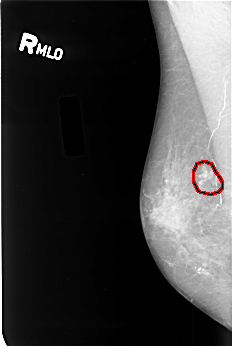

B_3380_1.RIGHT_MLO

RIGHT_MLO LINES 4496 PIXELS_PER_LINE 3024 BITS_PER_PIXEL 12 RESOLUTION 50 OVERLAY

FILE: B_3380_1.RIGHT_MLO.OVERLAY

TOTAL_ABNORMALITIES 1

ABNORMALITY 1

LESION_TYPE CALCIFICATION TYPE PUNCTATE-PLEOMORPHIC DISTRIBUTION CLUSTERED

LESION_TYPE MASS SHAPE IRREGULAR MARGINS ILL_DEFINED

ASSESSMENT 4

SUBTLETY 3

PATHOLOGY MALIGNANT

TOTAL_OUTLINES 1

BOUNDARY